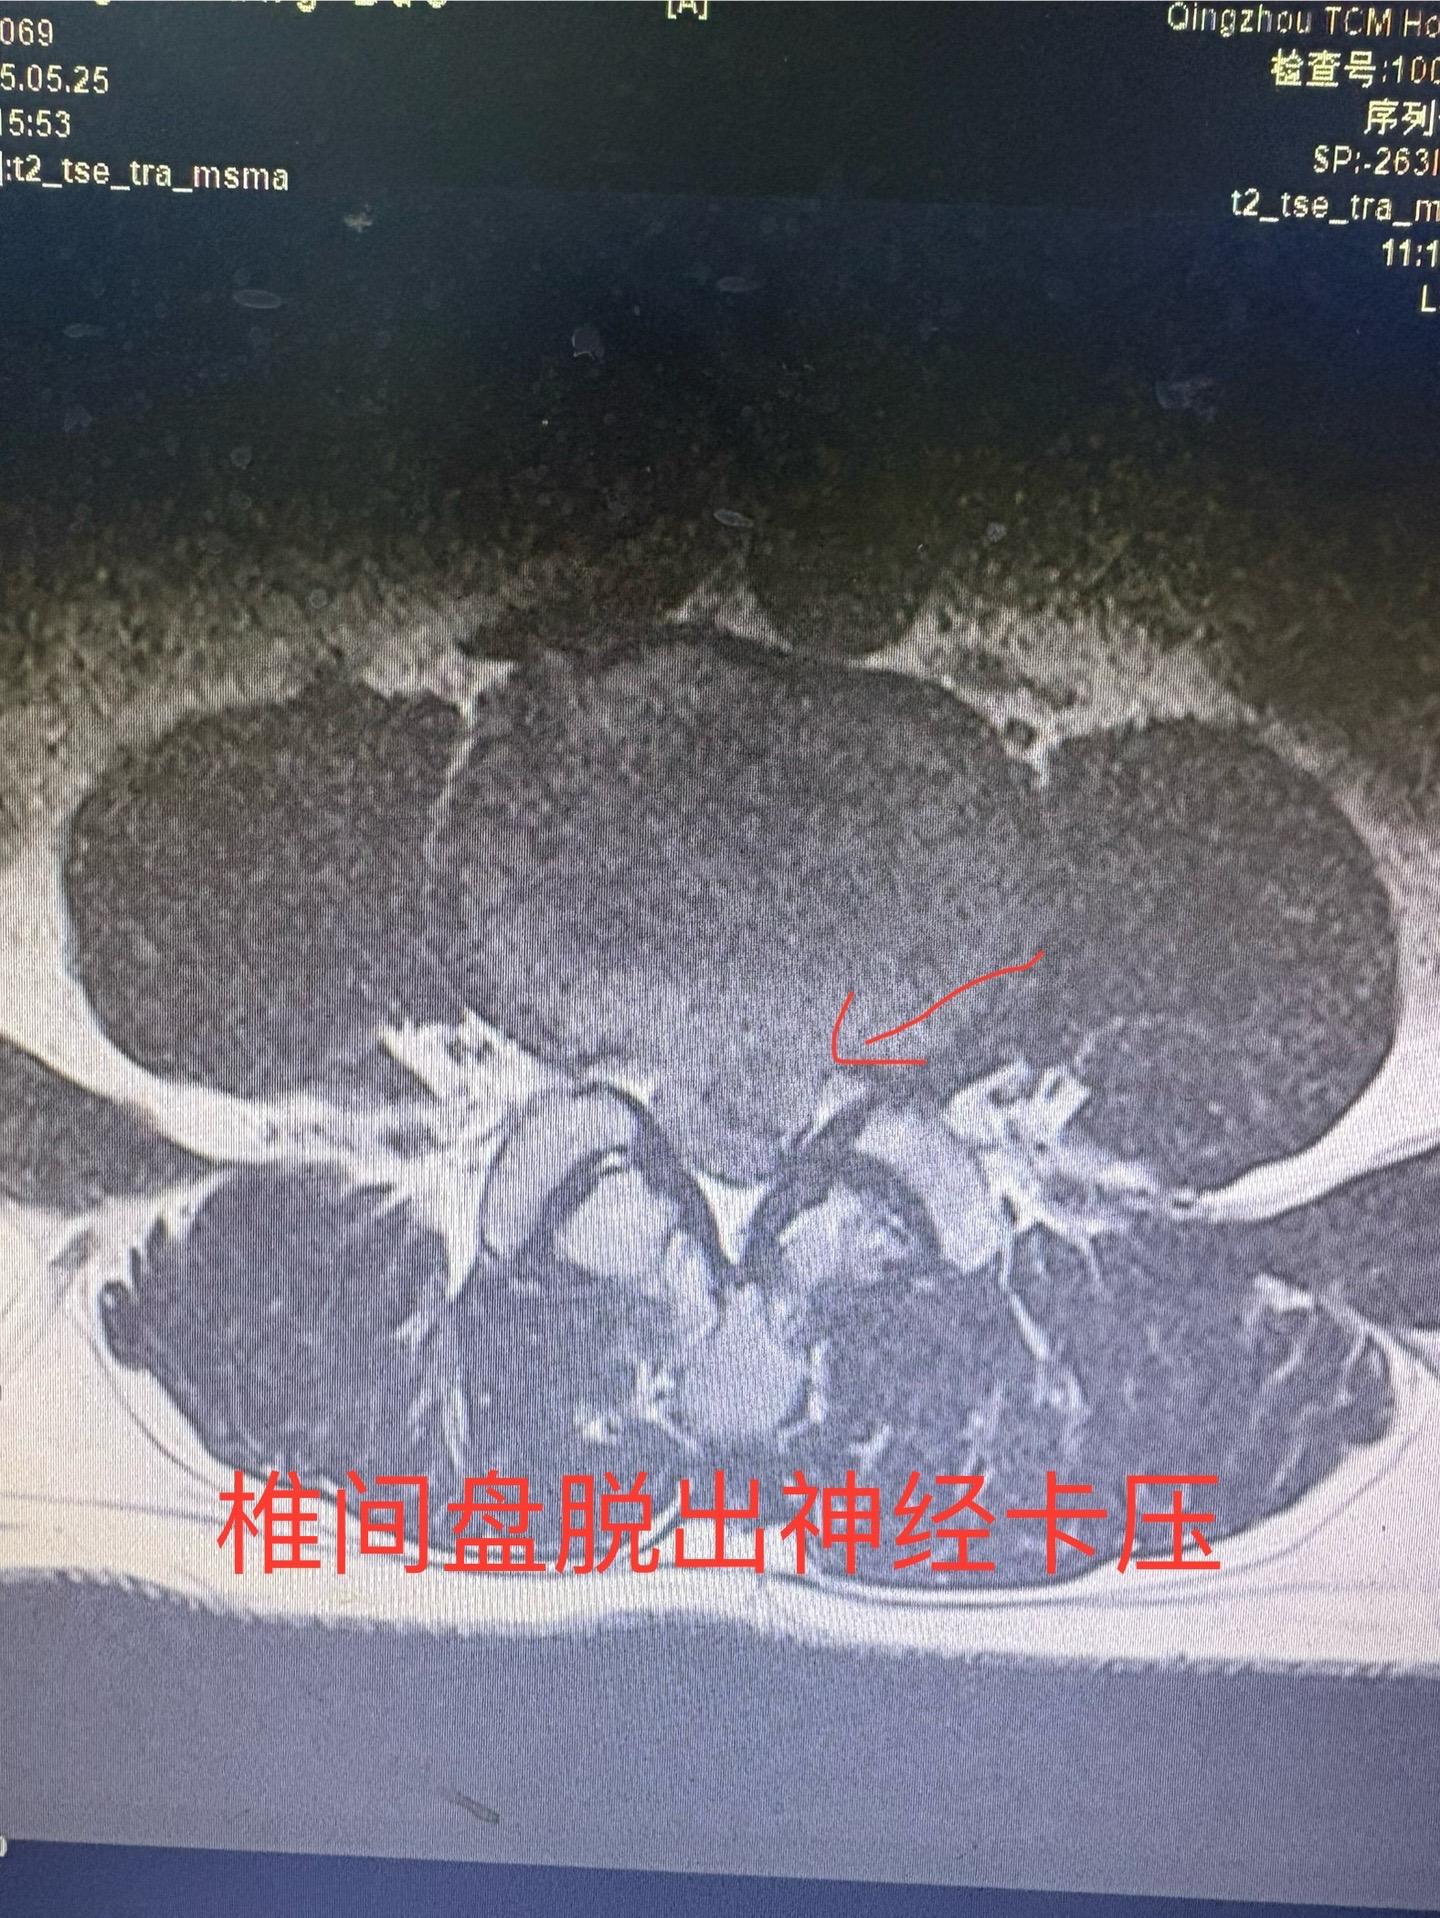

前段时间发现一例椎间盘突出病人保守治疗突出自行吸收,最近又发现一例治疗半年椎间盘突出已自行吸收,证明这不是个例。有部分人确实可以自行吸收,人的人体是很神奇的